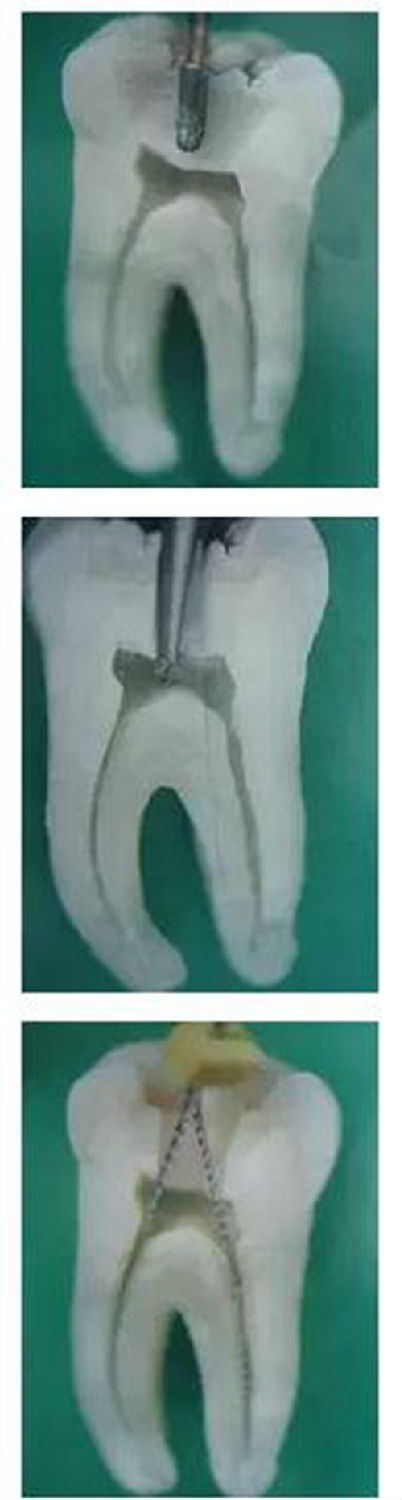

1,開髓:洞型是否制備的符合要求,髓室頂是否揭得剛剛好,沒有破壞洞壁及洞底結(jié)構(gòu)。。。

1.jpg

再次分享根管治療的點滴見解!再次分享根管治療的點滴見解!再次分享根管治療的點滴見解!

圖1,裂鉆鉆到近髓 2,球鉆穿髓 3,小號銼探查根管口

2.jpg

圖4,球鉆揭髓頂 5,修整洞型 6,完成開髓